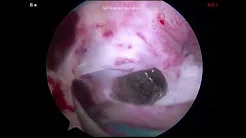

Osteochondral Proximal Tibial and Lateral Meniscal Allograft Transplant